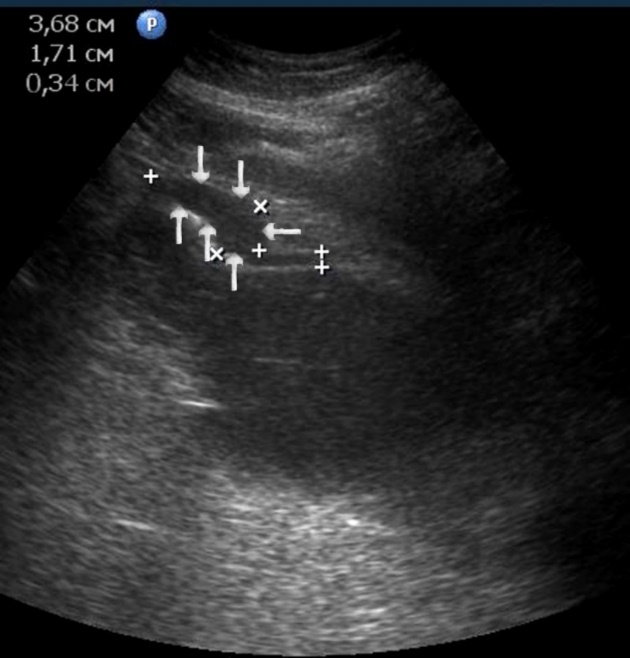

Figure 10.The gastric carcinoma of diffuse infiltrative form. An area with a local thickening up to 1,7 cm, a length of 3,68 cm, is visualized on the anterior wall of the antrum (arrows). The thickening of the normal stomach wall is 0,34 cm.

T3 stage of polypoid form was recorded in one case, ulcerative form – in 11 cases, infiltrative ulcerative forms – in 21 cases and diffused infiltrative forms – in 8 cases. The Sonographic features of infiltrative ulcerative form of gastric carcinoma was shown as local uneven thickening of the stomach wall with a length of up to several centimeters with intermittent images and ulceration of the mucosa (Figure 11). The Ulcerative form of gastric carcinoma was shown as a raised margins surrounded by a thickened gastric wall with irregular margins (Figure 12). Gastric carcinomas of diffuse infiltrative form is illustrated as a diffuse thickening of the muscle layer, a smooth contour, discontinuous mucosal image without ulceration and involvement of the serous membrane in the process (Figure 13).